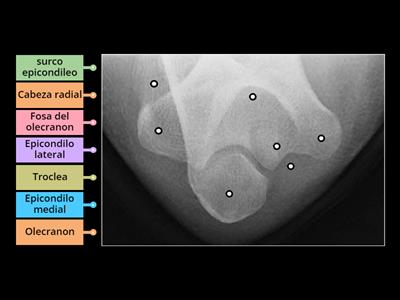

Anatomia rx proyeccion de olecranon